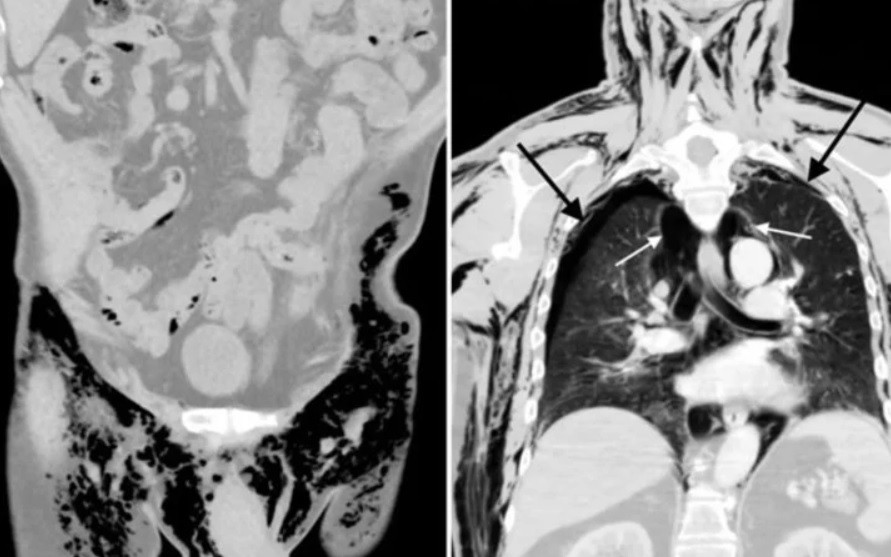

Análisis posteriores le detectaron un neumoescroto silbante, neumotórax bilateral, neumomediastino y enfisema subcutáneo.

Si bien no tuvo complicaciones al principio, tiempo después se le detectó un neumoescroto silbante, así como otras patologías derivadas de la acumulación de aire en el tórax.

Los análisis al paciente arrojaron también un neumotórax bilateral, una acumulación de aire en una cavidad entre los pulmones y el tórax conocida como cavidad pleural.

Asimismo, le detectaron neumomediastino, que se debe también a una acumulación del aire, esta vez en una cavidad ubicada entre los dos pulmones.

Y, por último, le diagnosticaron un enfisema subcutáneo a raíz de la penetración de aire en los tejidos ubicados bajo la piel.